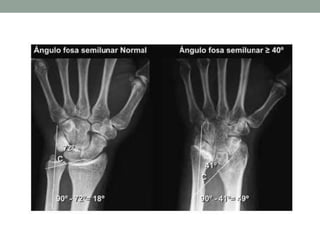

Diagnóstico Imagenológico

• McCarroll et al. 2010

• Tilt ulnar

• Subsidencia del semilunar

• Angulo de la fosa semilunar ≥ 40º

(90 – C)

• Ángulo entre foseta semilunar y eje

de la ulna

• Desplazamiento volar del carpo

Diagnóstico Imagenológico • McCarrollet al. 2010 • Tilt ulnar • Subsidencia del semilunar • Angulo de la fosa semilunar ≥ 40º (90 – C) • Ángulo entre foseta semilunar y eje de la ulna • Desplazamiento volar del carpo